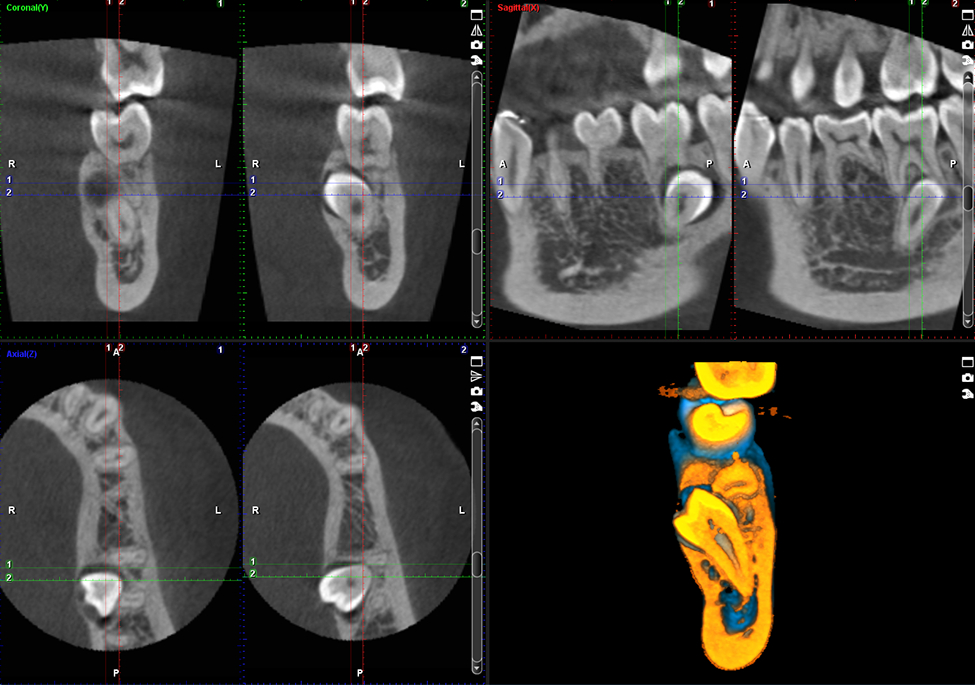

4 yếu tố có thể xác định chất lượng phim chụp:

• Grayscale: là phạm vi các sắc thái xám giữa trắng và đen. Trong X-quang, các sắc thái xám khác nhau cần phải được phân biệt rõ ràng để có thể nhìn thấy tốt các chi tiết.

• Gamma Correction: là cách tối ưu hóa việc sử dụng các bit trong hình ảnh để cho ra ánh sáng và màu sắc trung thực. Nếu không có hiệu ứng gamma, hình ảnh sẽ khác so với những gì chúng ta dự đoán – quá tối hoặc quá sáng, bị trôi, lệch màu,…

• Lumen (độ sáng): 1 bức ảnh chụp đủ độ sáng sẽ giúp xem được rõ ràng và chi tiết hơn.

• Resolution (Độ phân giải): liên quan đến voxel trên một thể tích ảnh, số lượng voxel càng nhiều, voxel càng nhỏ thì ảnh 3D càng rõ nét.